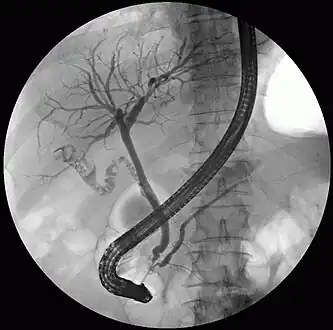

Common bile duct stone removal with a retrieval balloon

Treatment is removal of the gallstone from the bile duct using ERCP or an intraoperative cholangiogram. In these procedures, a thin tube is introduced into the common bile duct to perform a cholangiogram. If stones are identified, the surgeon inserts a tube with an inflatable balloon to widen the duct, and the stones are usually removed using either a balloon or tiny basket. A laser can be used to split big stones and make it easier to solve it using laparoscopy.[3]